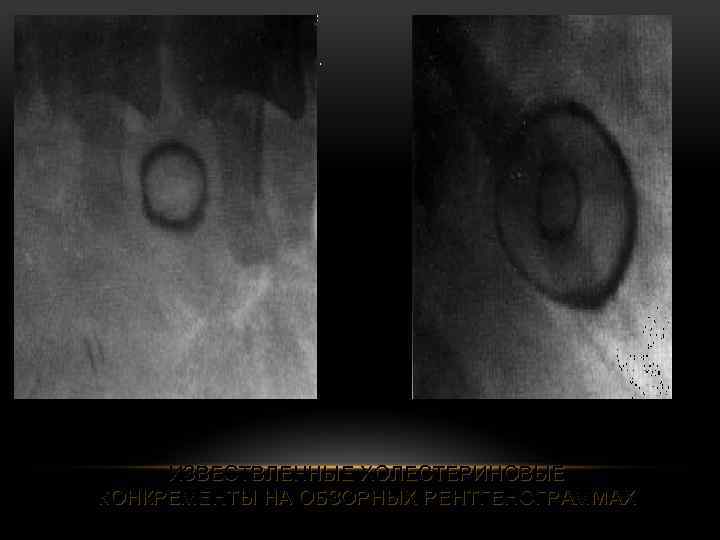

ИЗВЕСТВЛЕННЫЕ ХОЛЕСТЕРИНОВЫЕ КОНКРЕМЕНТЫ НА ОБЗОРНЫХ РЕНТГЕНОГРАММАХ

ИЗВЕСТВЛЕННЫЕ ХОЛЕСТЕРИНОВЫЕ КОНКРЕМЕНТЫ НА ОБЗОРНЫХ РЕНТГЕНОГРАММАХ